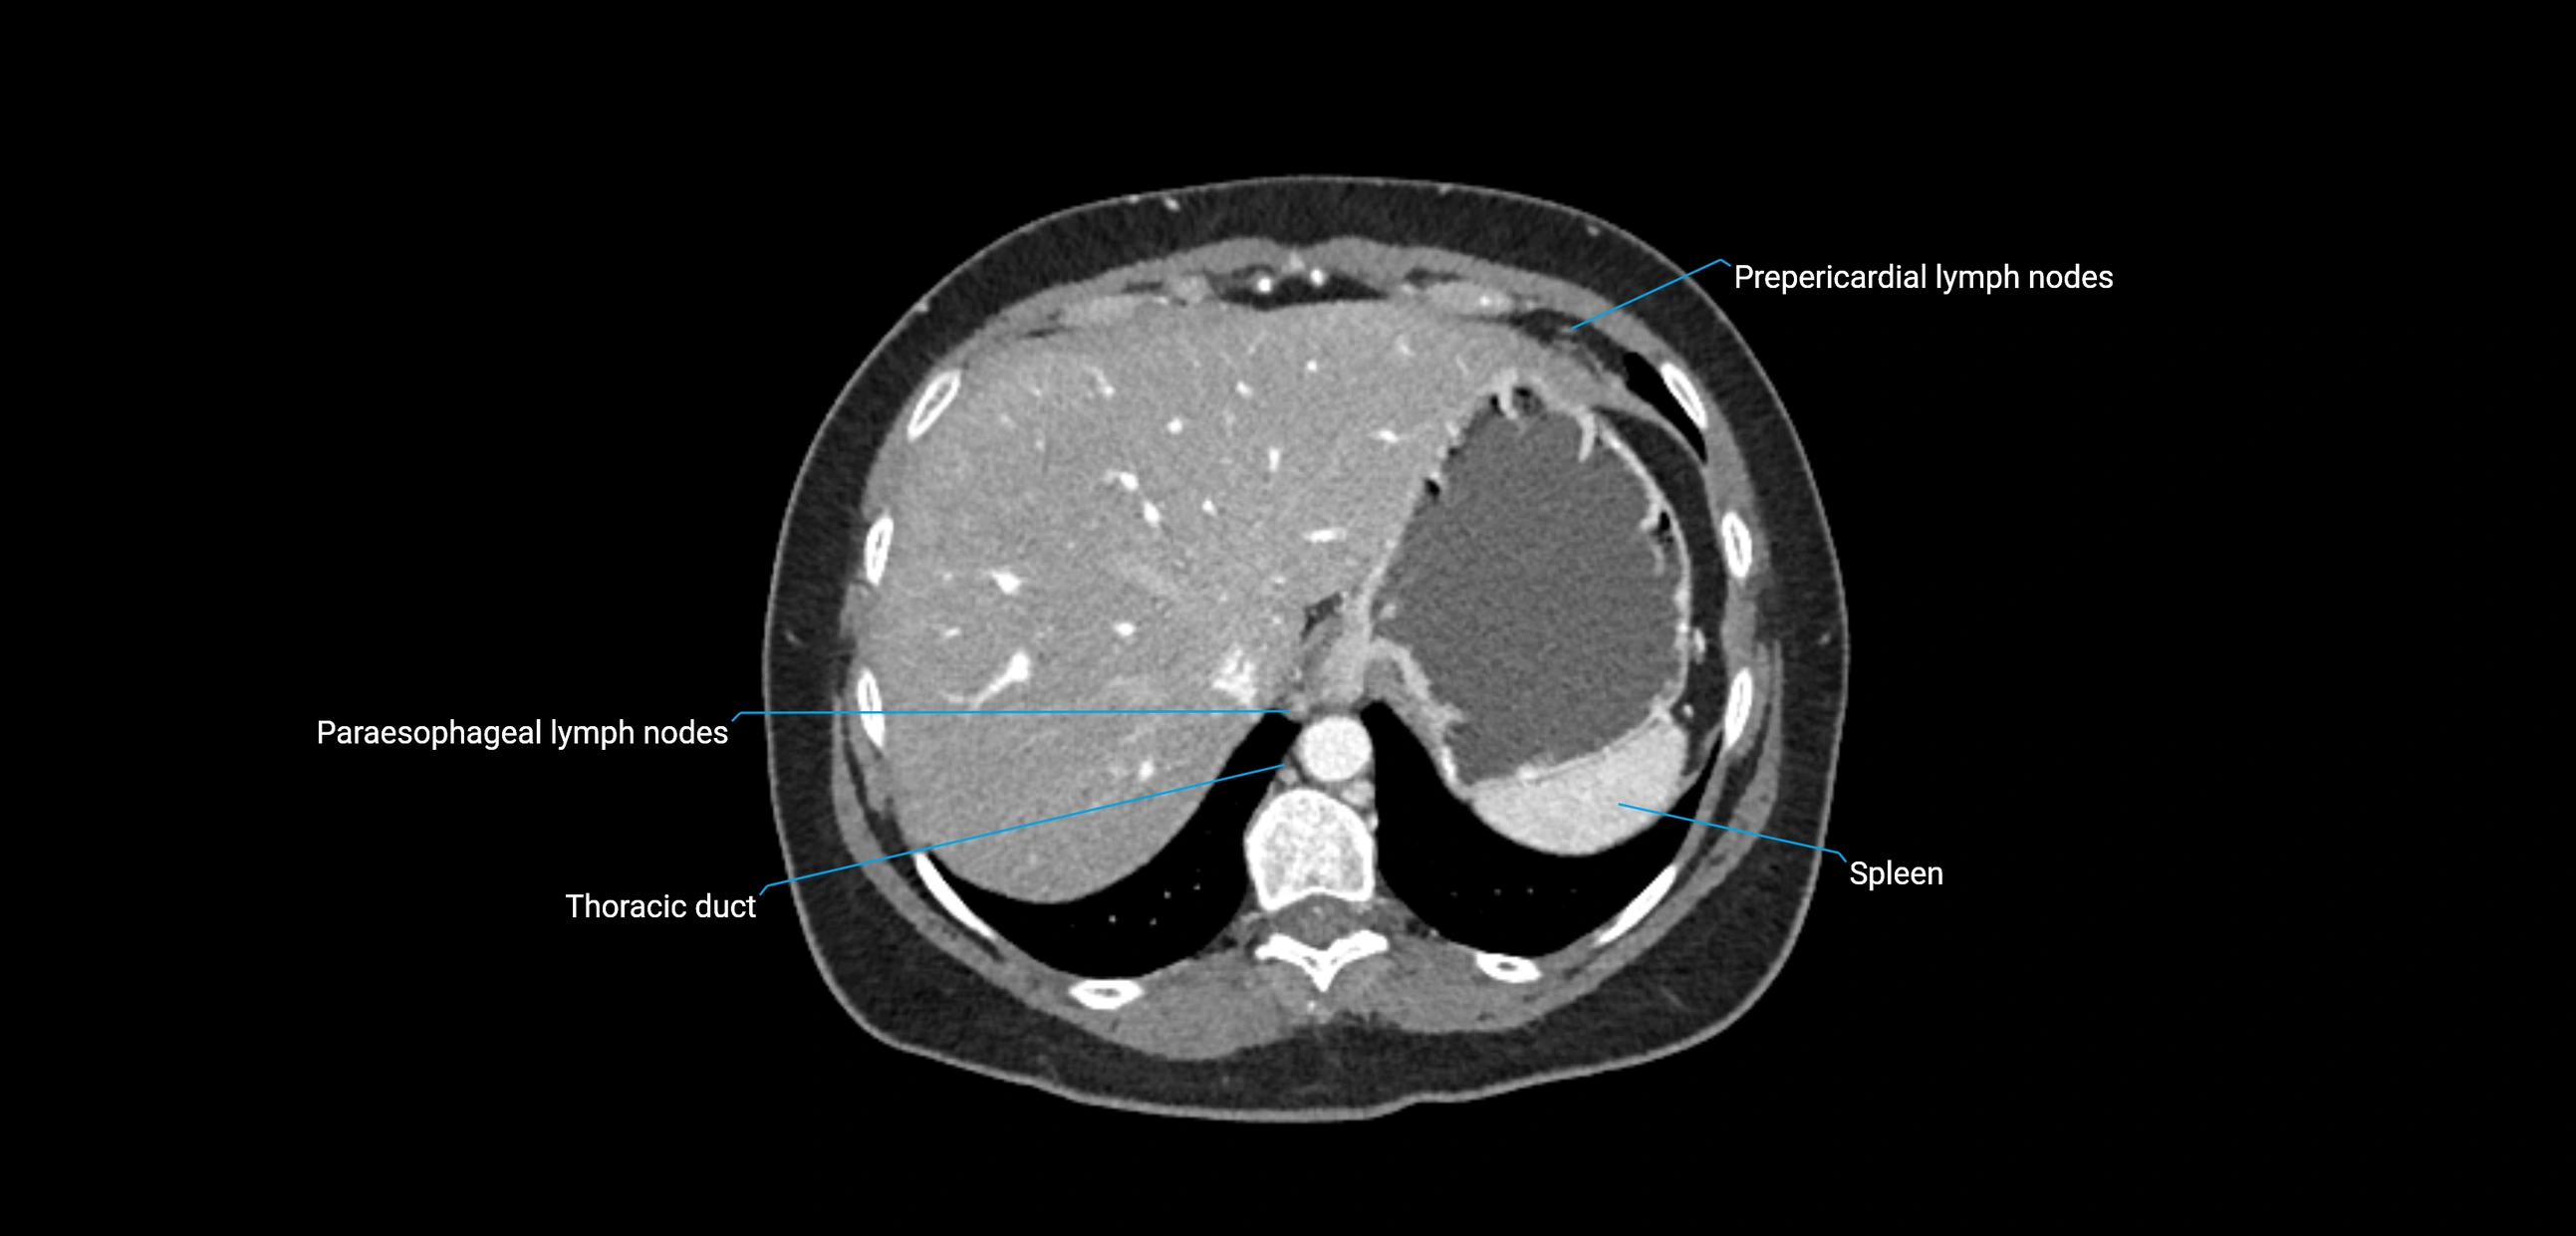

CT image

image